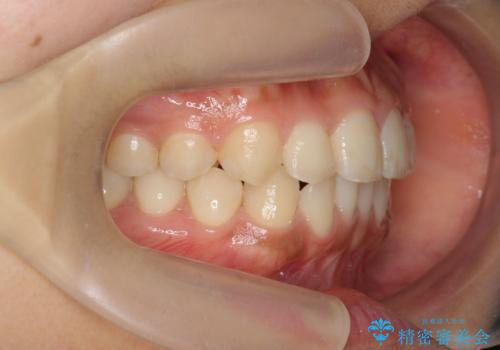

- 前歯のガタつき、上下たがい違いになっている歯並び(クロスバイト)の改善を求めて来院されました。

インビザラインによる矯正治療を行いますが、クロスバイトの改善をワイヤー部分矯正で事前に行うことにより治療期間の短縮する治療計画を立案します。